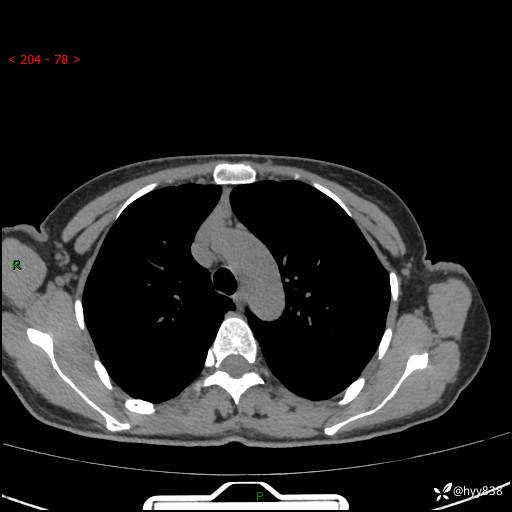

胸部CT平扫